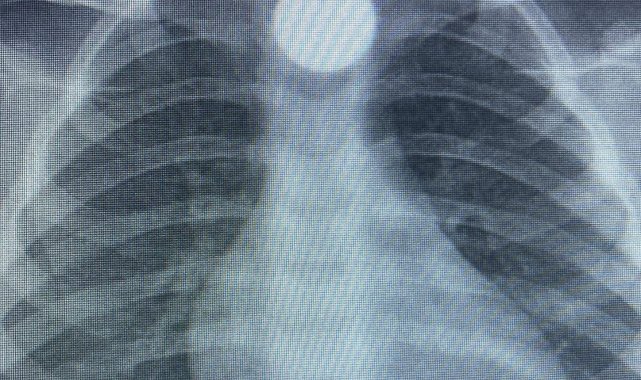

Olay, İnegöl'ün kırsal Yeniceköy Mahallesi'ndeki bir evde meydana geldi. 3 yaşındaki Bilal K., evde yerde bulduğu 50 kuruş madeni parayı ağzına atıp yuttu. Olayı fark eden ailesi tarafından çocuk özel araçla İnegöl Devlet Hastanesi'ne kaldırıldı. Yapılan tetkiklerde yemek borusunda takılı kalan madeni para görüldü. Çocuk ilk tedavinin ardından ambulansla Bursa Yüksek İhtisas Eğitim Ve Araştırma Hastanesi'ne sevk edildi.